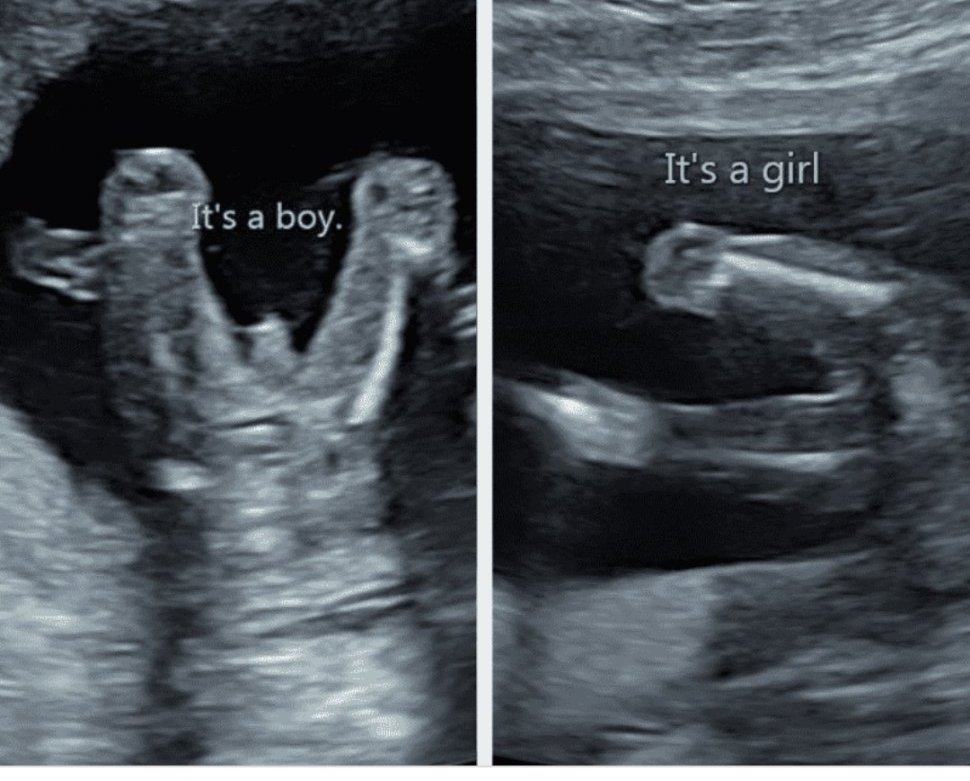

Кога може да се определи полът на бебето чрез ултразвук?

В ранните етапи на бременността, определянето на пола на бебето чрез ултразвук може да бъде предположетелно, но не категорично. Обикновено след 15-16-та седмица и при добра позиция на бебето, полът може да се види по-ясно. В ранните етапи, когато половите органи все още не са напълно развити, вероятността за точно определяне на пола е по-ниска.